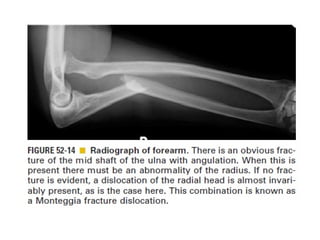

Skeletal trauma was presented by Dr Laith Fadhel with reference to Grainger's Diagnostic Radiology textbook. The presentation covered skeletal trauma as assessed through diagnostic radiology techniques. Key findings and treatments for skeletal injuries were likely discussed.